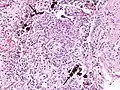

Asbestosis is the scarring of lung tissue (beginning around terminal bronchioles and alveolar ducts and extending into the alveolar walls) resulting from the inhalation of asbestos fibers. There are two types of fibers: amphibole (thin and straight) and serpentine (curly). All forms of asbestos fibers are responsible for human disease as they are able to penetrate deeply into the lungs. When such fibers reach the alveoli (air sacs) in the lung, where oxygen is transferred into the blood, the foreign bodies (asbestos fibers) cause the activation of the lungs' local immune system and provoke an inflammatory reaction dominated by lung macrophages that respond to chemotactic factors activated by the fibers.[19] This inflammatory reaction can be described as chronic rather than acute, with a slow ongoing progression of the immune system attempting to eliminate the foreign fibers. Macrophages phagocytose (ingest) the fibers and stimulate fibroblasts to deposit connective tissue. Due to the asbestos fibers' natural resistance to digestion, some macrophages are killed and others release inflammatory chemical signals, attracting further lung macrophages and fibrolastic cells that synthesize fibrous scar tissue, which eventually becomes diffuse and can progress in heavily exposed individuals. This tissue can be seen microscopically soon after exposure in animal models. Some asbestos fibers become layered by an iron-containing proteinaceous material (ferruginous body) in cases of heavy exposure where about 10% of the fibers become coated. Most inhaled asbestos fibers remain uncoated. About 20% of the inhaled fibers are transported by cytoskeletal components of the alveolar epithelium to the interstitial compartment of the lung where they interact with macrophages and mesenchymal cells. The cytokines, transforming growth factor beta and tumor necrosis factor alpha, appear to play major roles in the development of scarring inasmuch as the process can be blocked in animal models by preventing the expression of the growth factors.[20][21] The result is fibrosis in the interstitial space, thus asbestosis. This fibrotic scarring causes alveolar walls to thicken, which reduces elasticity and gas diffusion, reducing oxygen transfer to the blood as well as the removal of carbon dioxide. This can result in shortness of breath, a common symptom exhibited by individuals with asbestosis.[22]

The arrow points to an uncoated segment of asbestos fiber in this ferruginous body.

Severe pleural fibrosis with focal calcification.